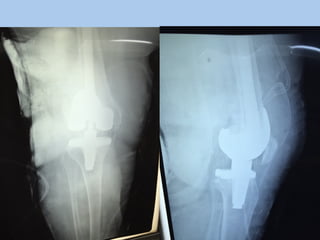

The document discusses a revision total knee replacement (TKR) surgery for a 65-year-old obese patient who had their initial surgery one year ago. They presented with inability to walk or bear weight and an exam finding of instability. Workup included testing for prosthetic joint infection (PJI) which guided intraoperative synovial fluid sampling. During surgery, a fracture was discovered and addressed. Key learning points emphasized preparation, following PJI guidelines, and teamwork.